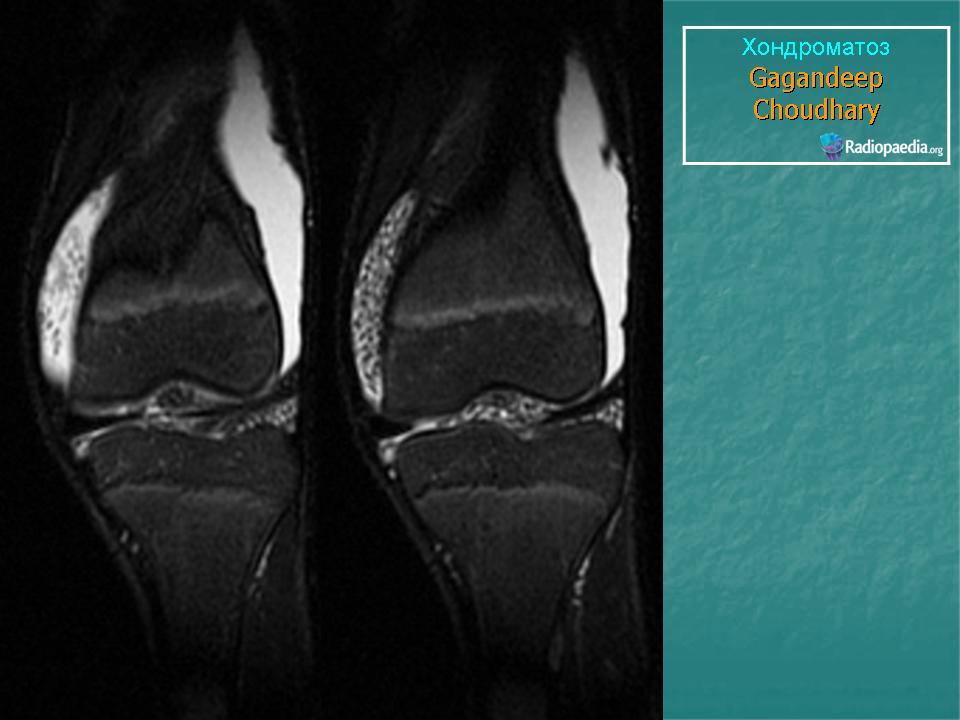

КСС. Хондроматоз внутрисуставной (синовиальный) 1. +

Хондроматоз внутрисуставной (синовиальный).

Хондроматоз

Хондроматоз внутрисуставной (синовиальный)

Хондроматоз суставов — хрящевая островковая метаплазия синовиальной оболочки

Синовиальный хондроматоз

Первичный синовиальный хондроматоз